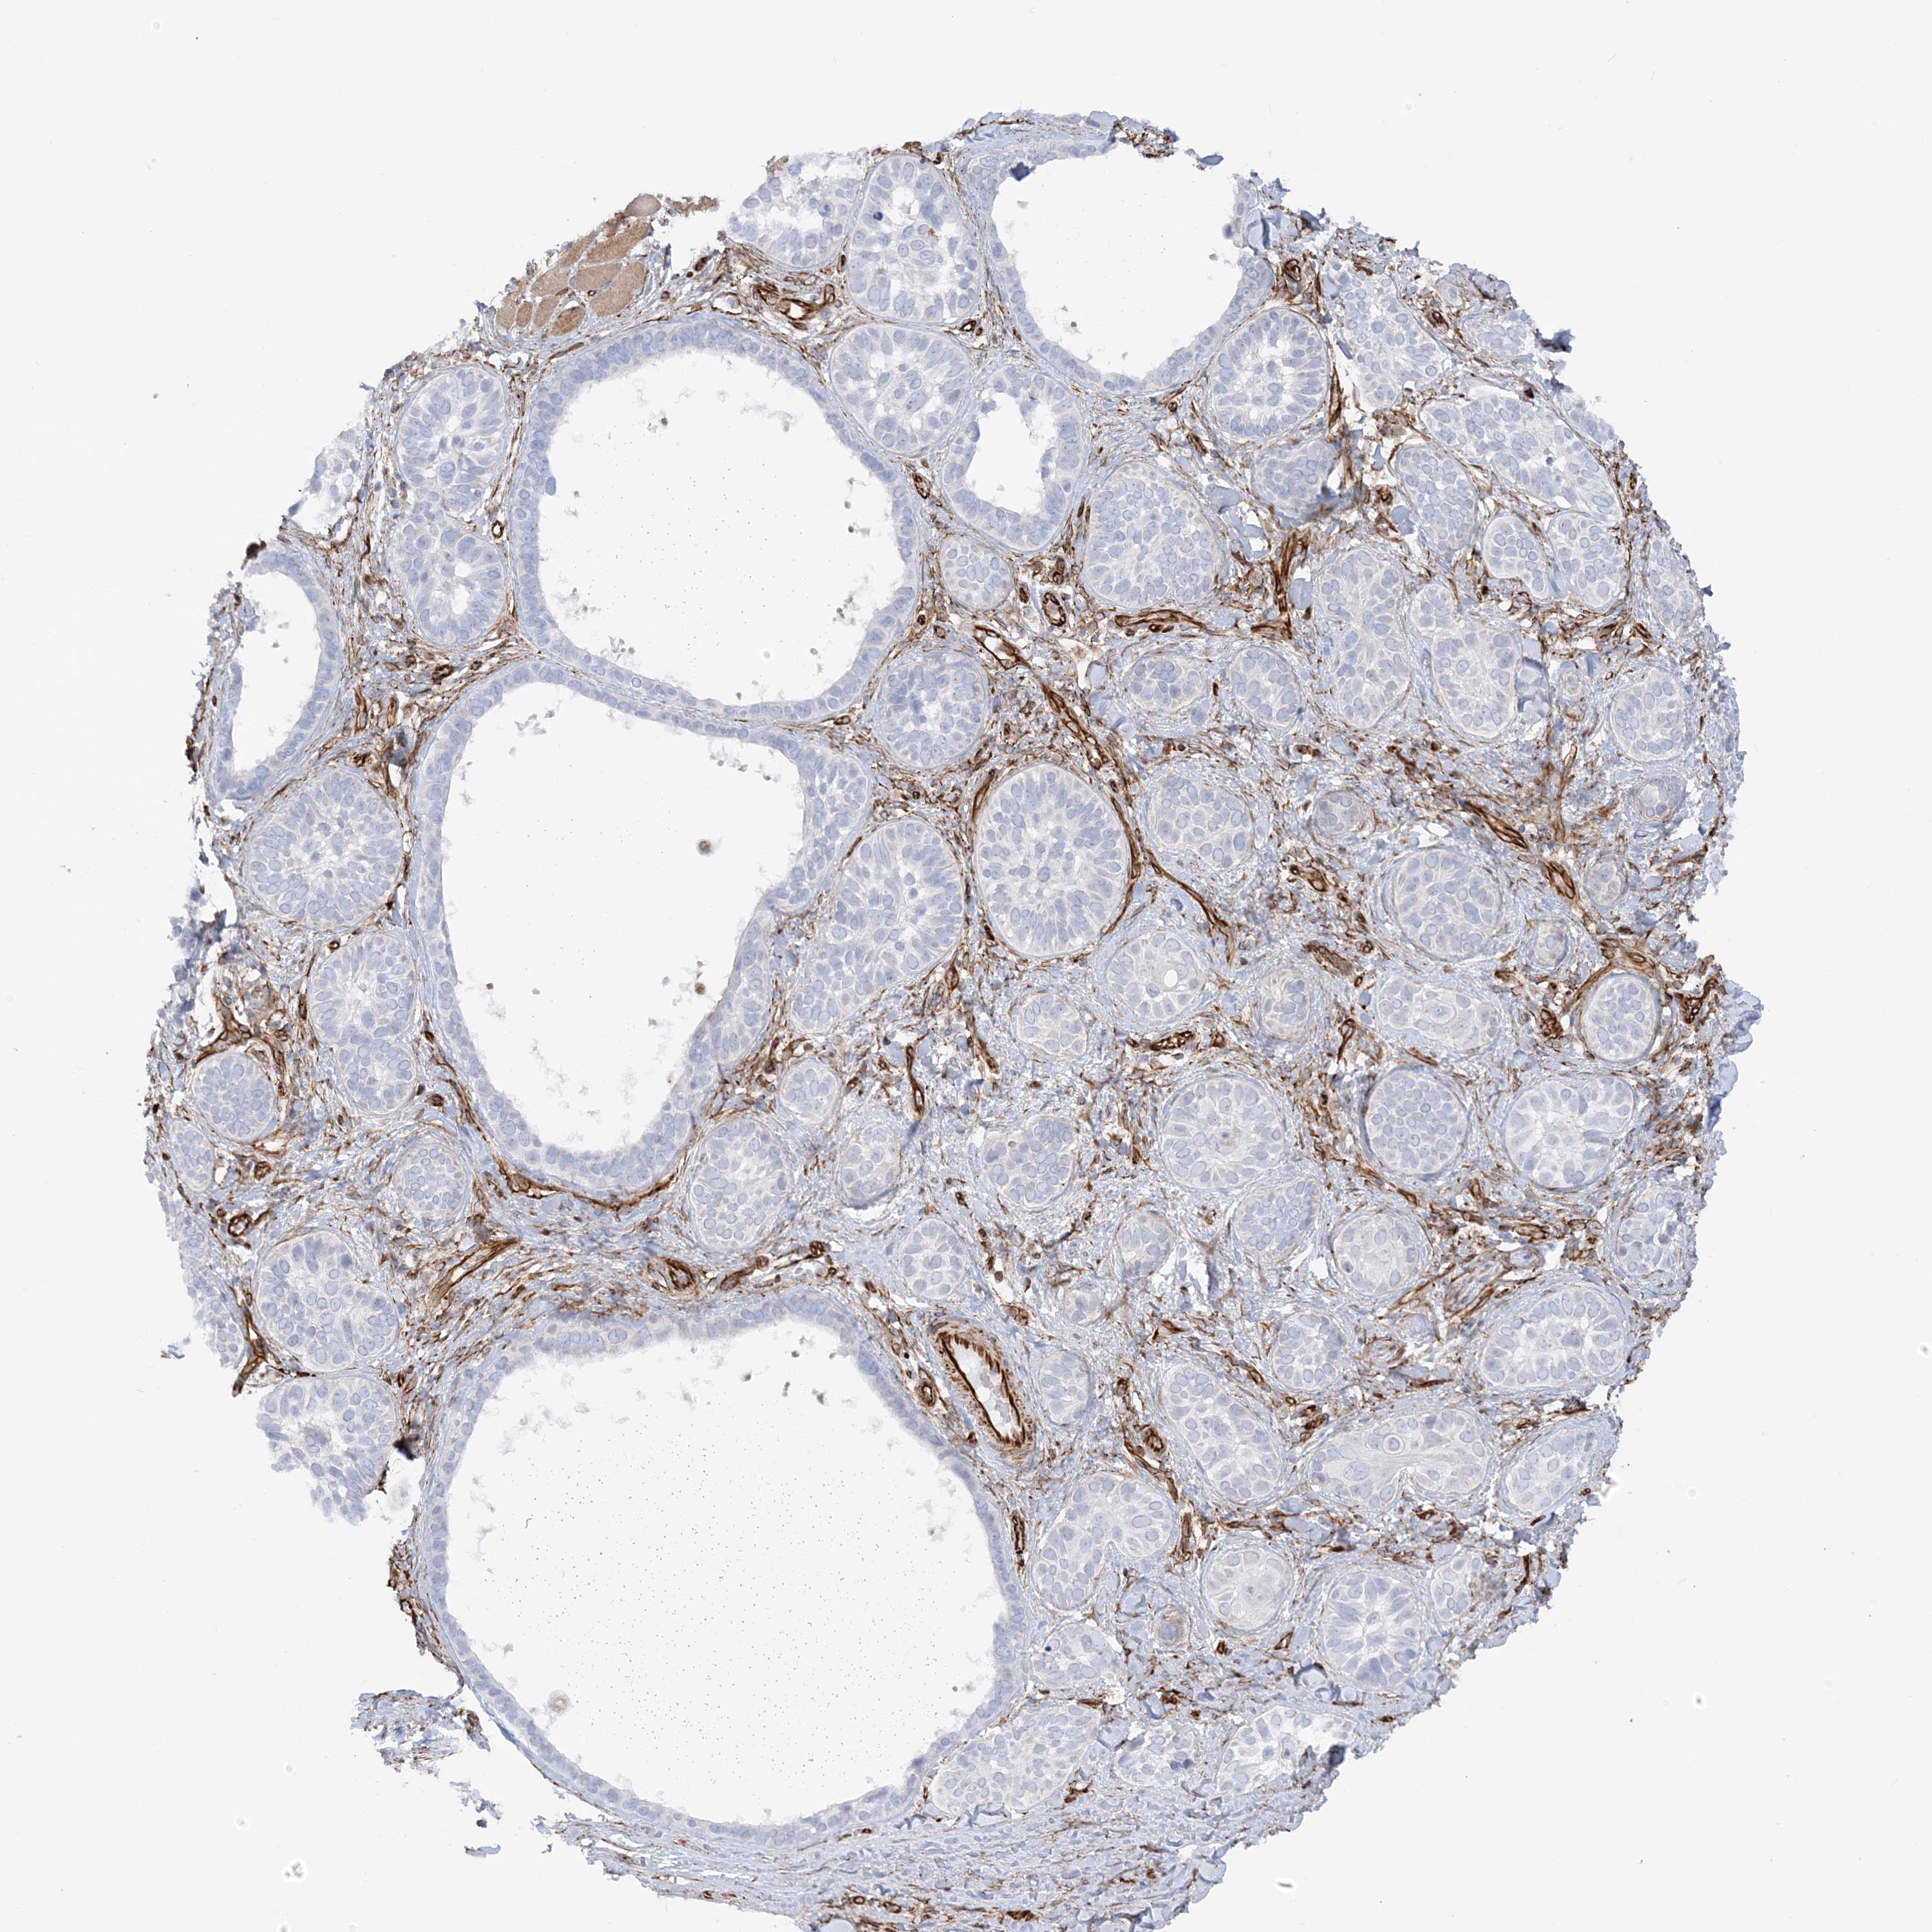

Basal cell and squamous cell cancer

SKIN CANCER - Protein expressioni

A mouse-over function shows sample information and annotation data. Click on an image to view it in a full screen mode. Samples can be filtered based on level of antibody staining by selecting one or several of the following categories: high, medium, low and not detected. The assay and annotation is described here.

Each image is clickable and will lead to virtual microscopy that enables deeper exploration of all samples and also displays staining intensity scores, fraction scores and subcellular localization as well as patient and tissue information for each sample.

Antibody HPA036560

Antibody HPA036561

Squamous cell carcinoma, NOS